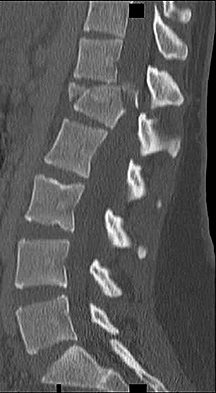

Figures 1 and 2 show a sagittal CT scan and a clinical photograph from a 16-

year-old boy who was found unresponsive after a diving accident. He had to be extricated from the bottom of a swimming pool by friends and was intubated at the scene by paramedics. In the emergency department, he was found to have weak triceps and grip strength bilaterally. Lower extremity strength was trace (grade 1 of 5). Sensation was diminished below the T2 dermatome. He had an absent bulbocavernosus reflex. Immediate open posterior reduction and stabilization were performed. Postoperative MRI revealed no iatrogenic disk herniation. Postoperative neurologic function revealed grade 4 strength in the triceps, wrist flexors, and bilateral grip. His lower extremity strength was grade 3. The sensory examination showed only slight diminution in the legs bilaterally. His bulbocavernosus reflex returned on postoperative day 2. On postoperative day 3, he required reintubation and was noted to require high positive end-expiratory pressures and a high ventilatory rate to keep him oxygenated. On postoperative day 4, his temperature was 38.7° C, blood pressure was 90/48, and pulse was 110 beats per minute. The urinary output measured 32 ml per hour. The white blood cell count was 14.8 with a left shift. A chest CT was ordered, and the results are shown in Figure 3. What best describes his condition?

4. Septic shock Discussion: D

Aspiration pneumonia developed, as seen on CT, and presumably occurred during his near drowning accident. His laboratory values and hemodynamic status are characteristic for septic shock. His original neurologic injury is an incomplete spinal cord injury, but after reduction and stabilization, he showed neurologic improvement, so this injury should not have contributed to his circulatory problems. The treatment for septic shock is broad spectrum antibiotics (species specific if the pathogen is identified) and pressors.